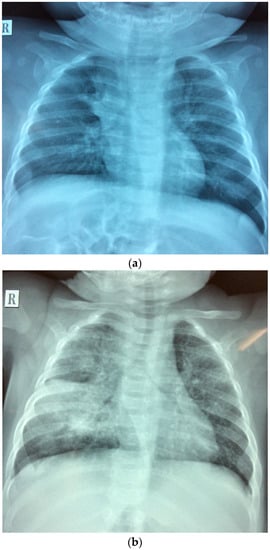

We admitted a 4-month-old girl (twin I) to the Da Nang Hospital for Women and Children, a provincial referral hospital in central Viet Nam. She presented to our outpatient department with prolonged coughing (around 2 weeks) without any fever or signs of respiratory distress. This persisted despite a 7-day course of oral erythromycin provided by a private paediatrician. She was hospitalized for further diagnostic evaluation. On admission, she weighed 6.2 kg, temperature 37 °C, breathing rate 50/min, heart rate 135 beats/min. On auscultation, her breath sounds were symmetric with a few dispersed crackles and no audible wheezing. Initial investigations, including full blood count and C-reactive protein (CRP), were all in the normal range. However, her chest X-ray (Figure 1a) was suggestive of lymph nodes in the right hilum and mediastinum. A Gene X-pert® test performed on a gastric aspirate (on admission) was positive for M. tuberculosis complex, without any rpo-B mutations suggestive of rifampicin resistance. The baby was diagnosed with active tuberculosis (TB), and was started on treatment with first-line TB drugs—isoniazid, rifampicin, pyrazinamide and ethambutol—as well as pyridoxine supplementation. The index case was discharged home after 2 weeks in hospital, having demonstrated good drug tolerance and no clinical signs of meningitis or progressive disease. Care will be closely supervised by the local TB clinic with follow-up by doctors at the Tuberculosis and Lung Diseases Hospital in Da Nang, with visits occurring every two weeks during the intensive phase of treatment, and then monthly.

Figure 1. Chest radiographs of (a) the index case (twin I) and (b) the infant sibling (twin S) at the time of tuberculosis diagnosis.

One month later, twin S developed a cough and fever at 3 months of age. She was treated with oral cefuroxime for 10 days, but without any clinical response. She was admitted to Da Nang hospital for Women and Children (the same hospital where twin I was admitted) and diagnosed with pneumonia based on her persistent coughing and chest radiograph abnormalities (Figure 1b). However, she had no signs of acute respiratory distress and all routine investigations were unremarkable. She was given intravenous cefotaxime for 11 days, as well as intravenous gentamycin for 7 days followed by oral erythromycin for 7 days. In the absence of clinical improvement, a high resolution computed tomography (CT) scan of the chest was performed. This revealed multiple nodes in the right hilum and mediastinum. In retrospect, this was visible on the initial chest X-ray, which also suggested possible miliary spread. At this point the mother admitted that she was currently on TB treatment. A Gene X-pert® test performed (2 weeks after admission) on a gastric aspirate was positive for M. tuberculosis, without evidence of rifampicin resistance. She had no signs suggestive of meningitis and was started on first-line TB treatment.